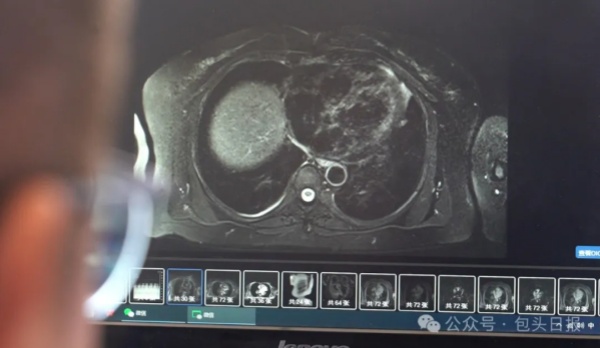

Hospitals in Baotou open medical test result sharing. [Photo/WeChat account of Baotou Daily]

"Shared test results improve diagnostic efficiency and reduce costs. For imaging exams like MRI and CT scans, we can now access dynamic images instead of relying on static reports, giving us a clearer and more detailed view of a patient's condition," said Dr Liu Kaiyuan from the Baogang Group Third Staff Hospital.